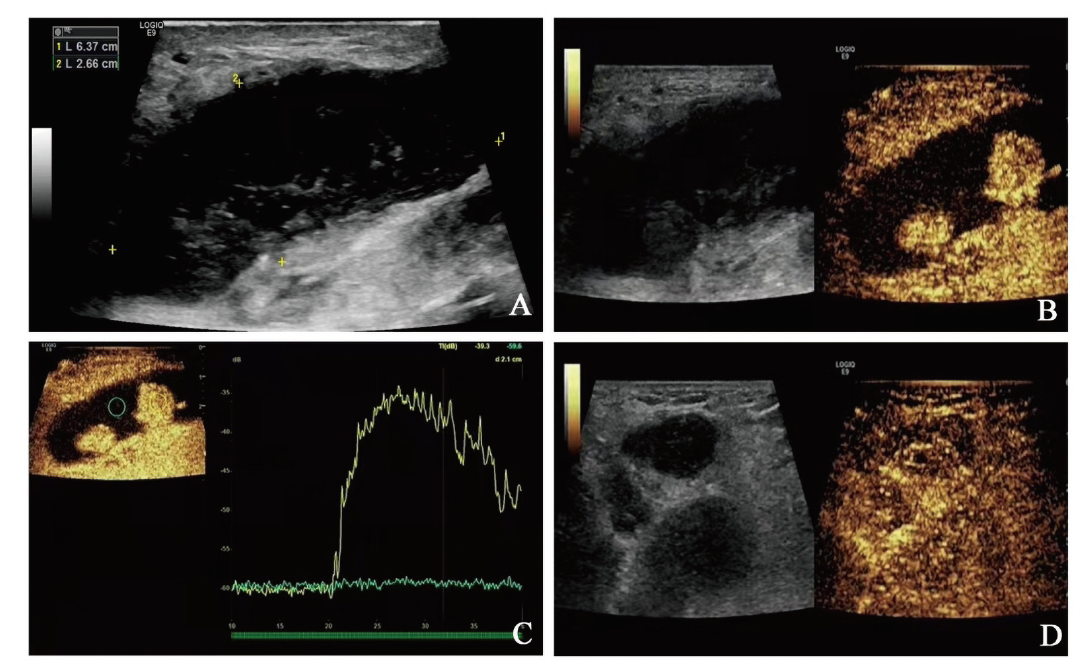

超声造影:于患者左侧肘正中静脉团注造影剂声诺维(SonoVue) 2.4 mL×1次,然后用5 mL生理盐水冲管。观察左侧腹股沟肿大程度最大的淋巴结,可见该淋巴结造影强度呈高增强,造影后12 s左侧腹股沟淋巴结造影呈弥漫性增强,20 s增强达峰值,30 s造影剂消退,淋巴结内部造影呈不均匀增强,部分区域(面积较大)造影始终未增强(图1A、B)。通过超声诊断仪绘制时间-信号强度曲线(TIC)(图1C)。30 min后于患者左侧肘正中静脉追加造影剂SonoVue 1.2 mL×1次,然后用5 mL生理盐水冲管,观察右侧腹股沟肿大程度最大的淋巴结,可见该淋巴结造影强度呈高增强,造影后10 s右侧腹股沟淋巴结造影开始呈离心性均匀增强,19 s增强达峰值,增强过程呈“雪花样”改变,30 s造影剂消退,呈快进快退(图1D)。造影结果提示淋巴瘤伴坏死可能,不排除转移性肿瘤可能,遂于超声引导下对造影高增强区域实行穿刺(图2A)。

图1 一例浅表淋巴瘤伴坏死患者的超声造影

注:A~C可见左侧腹股沟最大淋巴结有筛网样回声,造影见大片未增强区域,TIC示坏死部位无增强;D可见右侧腹股沟淋巴结造影呈典型“雪花样”改变。